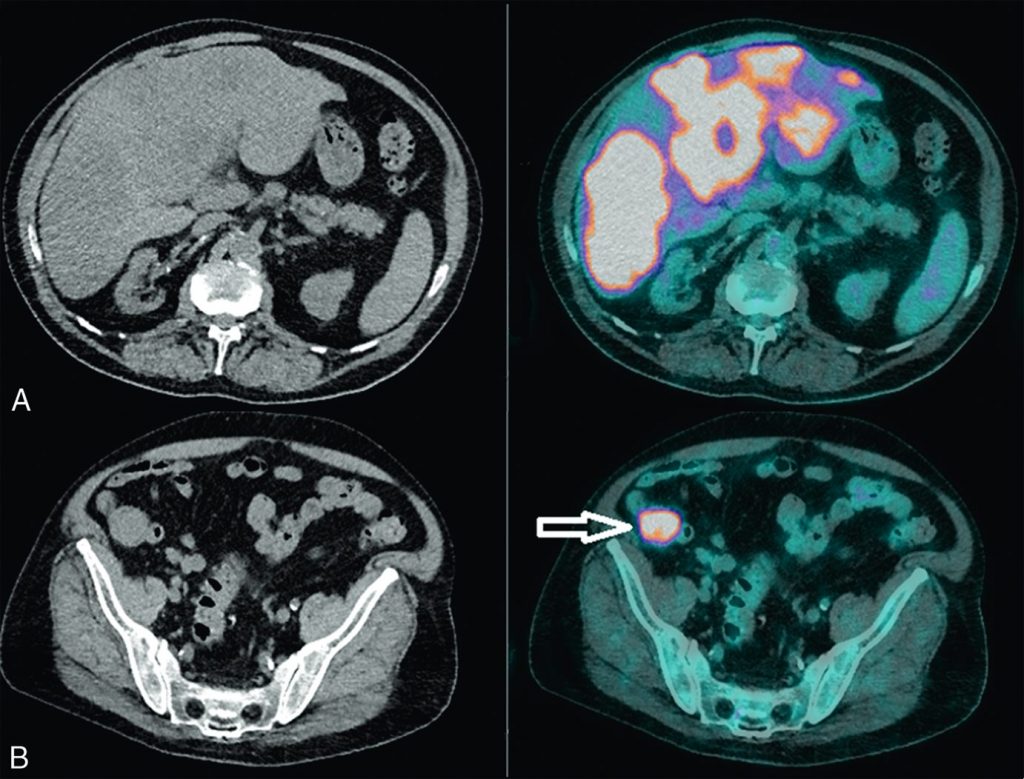

La TEP-TDM au 18FDG est indiquée pour le bilan d’extension des lésions intrahépatiques suspectes de lésions secondaires, à la recherche d’une tumeur primitive, si les examens standards sont non contributifs (mammographie, FOGD et colonoscopie), ainsi que pour la détection des métastases extrahépatiques, en montrant une hyperfixation (figure 16.5).

Fig. 16.5. Images en coupes axiales de TDM (à gauche) et TEP au 18FDG fusionnées à la TDM (à droite) réalisées pour recherche d’une tumeur primitive dans un contexte de foie multimétastatique confirmant les multiples lésions hypermétaboliques hépatiques suspectes (A) et mettant en évidence un hypermétabolisme suspect d’un processus tissulaire au sein du cæcum (B, flèche). L’analyse anatomopathologique de cette lésion après exérèse est en faveur d’un adénocarcinome.

Source : CERF, CNEBMN, 2022.